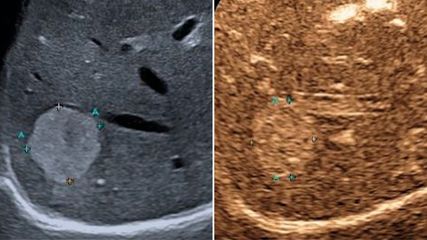

Sonografie der Leber – aktuelle Entwicklungen, quantitative Verfahren und klinische Bedeutung

Der vorliegende Übersichtsartikel fasst aktuelle technische Entwicklungen sowie klinische Anwendungen und Limitationen der Lebersonografie zusammen und diskutiert deren Stellenwert im ...